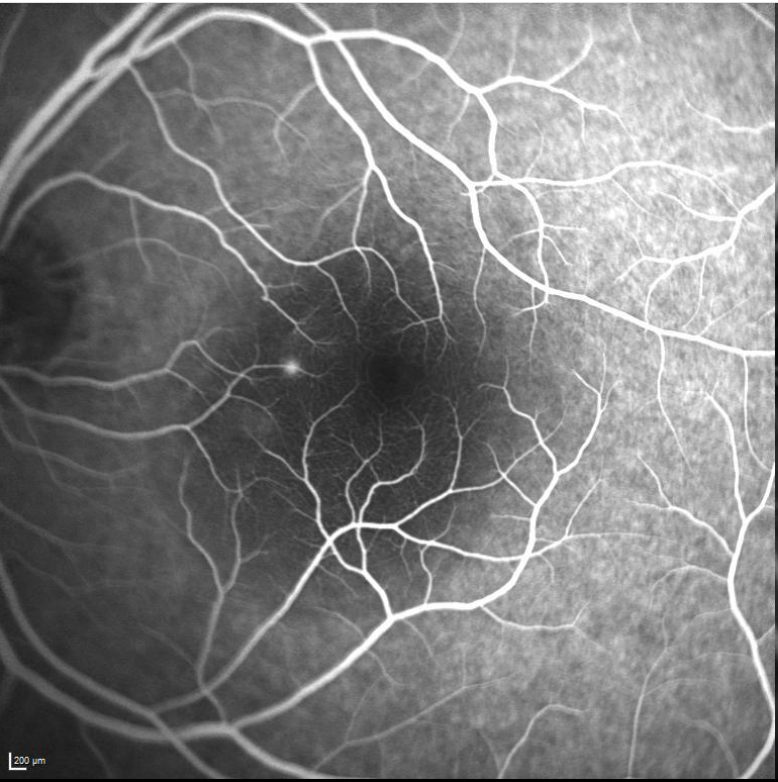

En la angiografía fluoresceínica se observa una arquitectura vascular normal. Característico de esta patología, se aprecia un punto de fuga del colorante nasal a la mácula con tinción en mancha de tinta.